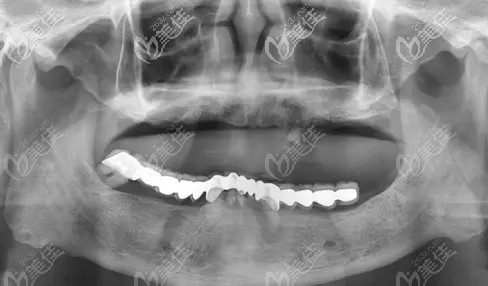

?56歲牙齒三度松動(dòng)醫(yī)生建議做種植牙,想問下5萬塊錢能做韓國登騰allon4全口種植牙嗎?

我牙齒一直不好,前段時(shí)間去醫(yī)院檢查,醫(yī)生說我的牙齒已經(jīng)三度松動(dòng)了,建議還是做全口種植牙,但是我還是猶豫了,因?yàn)樽约旱难例X還沒有脫落不想拔牙。不過這段時(shí)間發(fā)現(xiàn)牙齒已經(jīng)基本不能咬東西了,思來想去還是得做種植牙,然后就在網(wǎng)看好多人說韓國登騰allon4全口種植牙效果不錯(cuò),性價(jià)比也高,不知道5萬元能不能做?